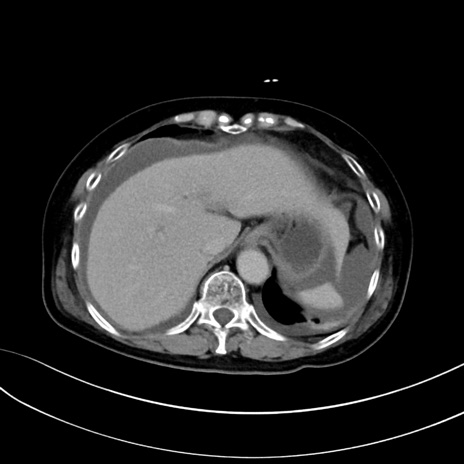

(冠状断像)1日半後